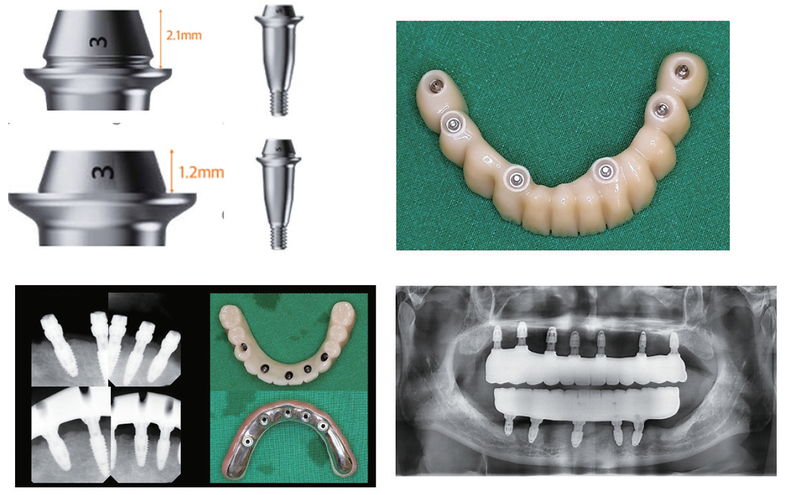

FOXDEN의 Z-plus와 X Abutment는 기존 시스템의 한계를 임상적으로 보완한 Cementless Abutment 시스템이다. 36도 이내 식립 시 별도의 각도 조절 없이 one-piece screw-retained 보철이 가능하며, 보철 단계에서의 선택지를 단순화해 준다. 실제 임상에서 수술 후 ‘이 케이스가 보철적으로 가능할지’를 다시 고민하지 않아도 된다는 점은 술자 입장에서 큰 장점으로 다가온다.

특히 스크루 홀 외벽에 경사를 부여해 보철물과 어버트먼트가 직접 접촉하도록 설계된 구조는 인상적이다. 이를 통해 교합력이 스크루에만 집중되지 않고 어버트먼트 전체로 분산되며, 보철물 장착 시 안정적인 안착감을 제공한다.

Z-plus Abutment는 Margin 두께를 충분히 확보해 밀링 과정이나 장착 후 파절 위험을 줄였고, X Abutment는 수직벽 길이를 늘려 술자의 선호와 케이스에 맞는 선택이 가능하도록 했다.

5. Digital Workflow와 결합한 임상 효율

수술 후 Cuff를 선택해 Abutment를 연결하고 스캔바디 체결만으로 바로 디지털 인상이 가능하다. 즉시 디자인 후 3D 프린팅을 통해 임시 보철 제작이 가능해, 전악 수술 후 3시간 이내 즉시 로딩이 가능해졌다.

최근 이마고웍스의 AI 디자인 모듈(Roydent 제공)을 적용하면서 디자인 시간 또한 절반 이상 단축됐고, 현재는 전악 수술 후 1주 이내 지르코니아 최종 보철 완성까지 진행하고 있다.